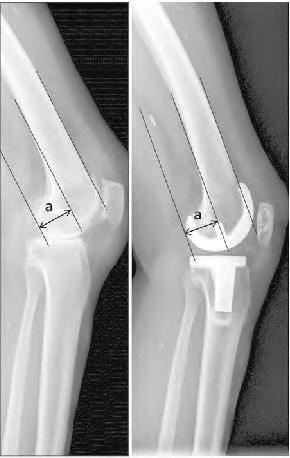

A 72-year-old female presents with progressive left thigh and knee pain for the last year. 5 years ago she sustained a femoral neck fracture treated with the implant seen in Figures A-C (current radiographs). The thigh pain is worse with weight-bearing. C-reactive

protein and erythrocyte sedimentation levels are within defined limits. Which of the following is the most likely cause of her pain?